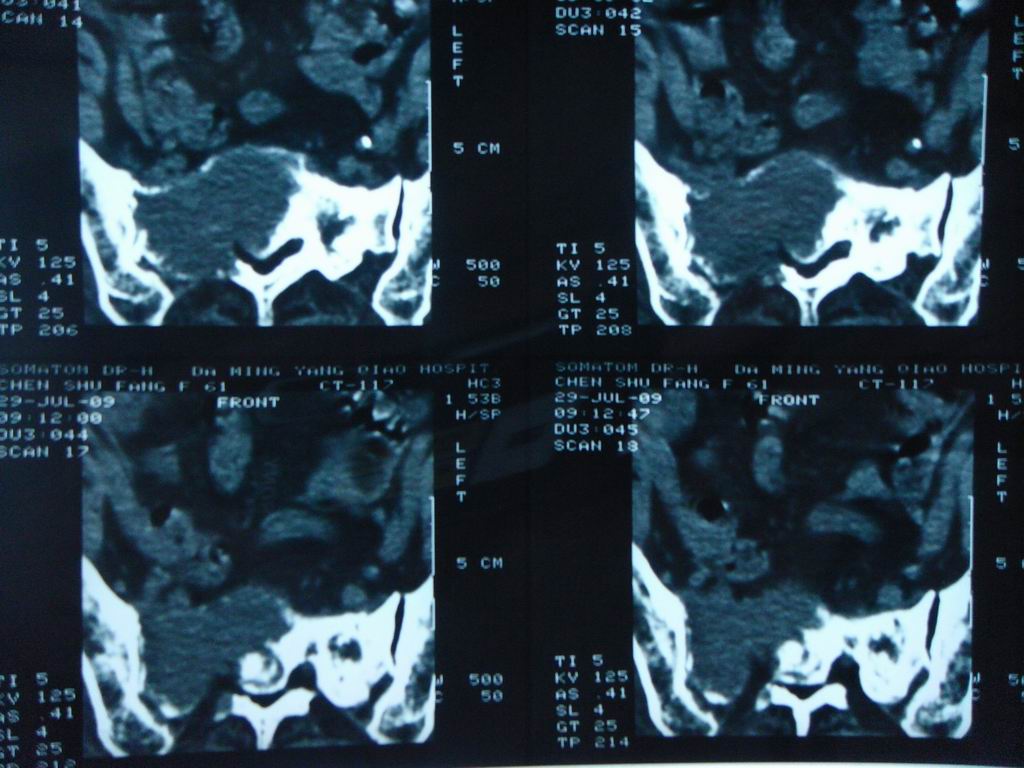

标题: CT21430:女性65岁 乳腺癌术后3年 [打印本页]

标题: CT21430:女性65岁 乳腺癌术后3年

结合病史,考虑骶骨转移瘤,但软组织肿块未突破骨壳,骨巨细胞瘤不能完全排除,骨髓瘤及脊索瘤不考虑。

结合病史,考虑骶骨转移瘤。

结合病史,考虑骶骨转移瘤。其它椎体,如腰5是否有问题呢?

个人感觉骨巨细胞瘤可能性大些。